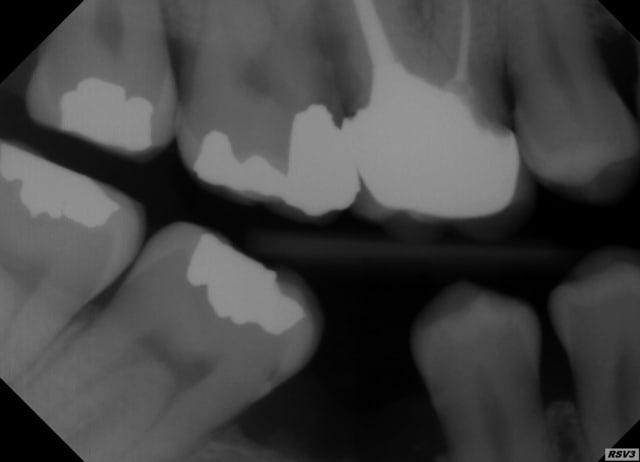

Pour mon cas (voir radio), ça sera exo et 2 implants.

Je relance le sujet, pour savoir comment vous traiteriez cette petite carie sous-gingivale sur 47 ?

Tu ne vois que la carie ?

Je vois une résorption importante de 45, une 46 absente, et une 47-48 qui se couchent

Non je ne vois pas que ça, d'ailleurs il a une poche paro de 10mm qu'on ne voit pas très bien autour de la 16, en plus de toutes tes observations.